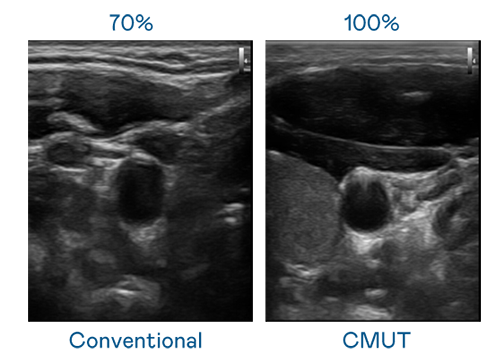

CMUT 技術是一種用電容式微機電元件來產生超音波訊號的技術。與傳統 PZT 壓電式技術相比,CMUT 頻寬增加 30%,更寬頻的超音波訊號讓影像解析度大幅提升,是實現高影像品質醫療超音波掃描、促進精準醫療發展的關鍵技術。

大頻寬帶來超清晰影像

超音波影像的解析度高低,首先取決於探頭能發出的訊號頻寬。d88尊龙z6 CMUT 可提供高清晰的超音波訊號,提供高頻寬、高靈敏度、影像紋理細節更高的超音波影像,協助醫護人員縮短影像判讀時間及利用精準的醫療影像進行診斷。